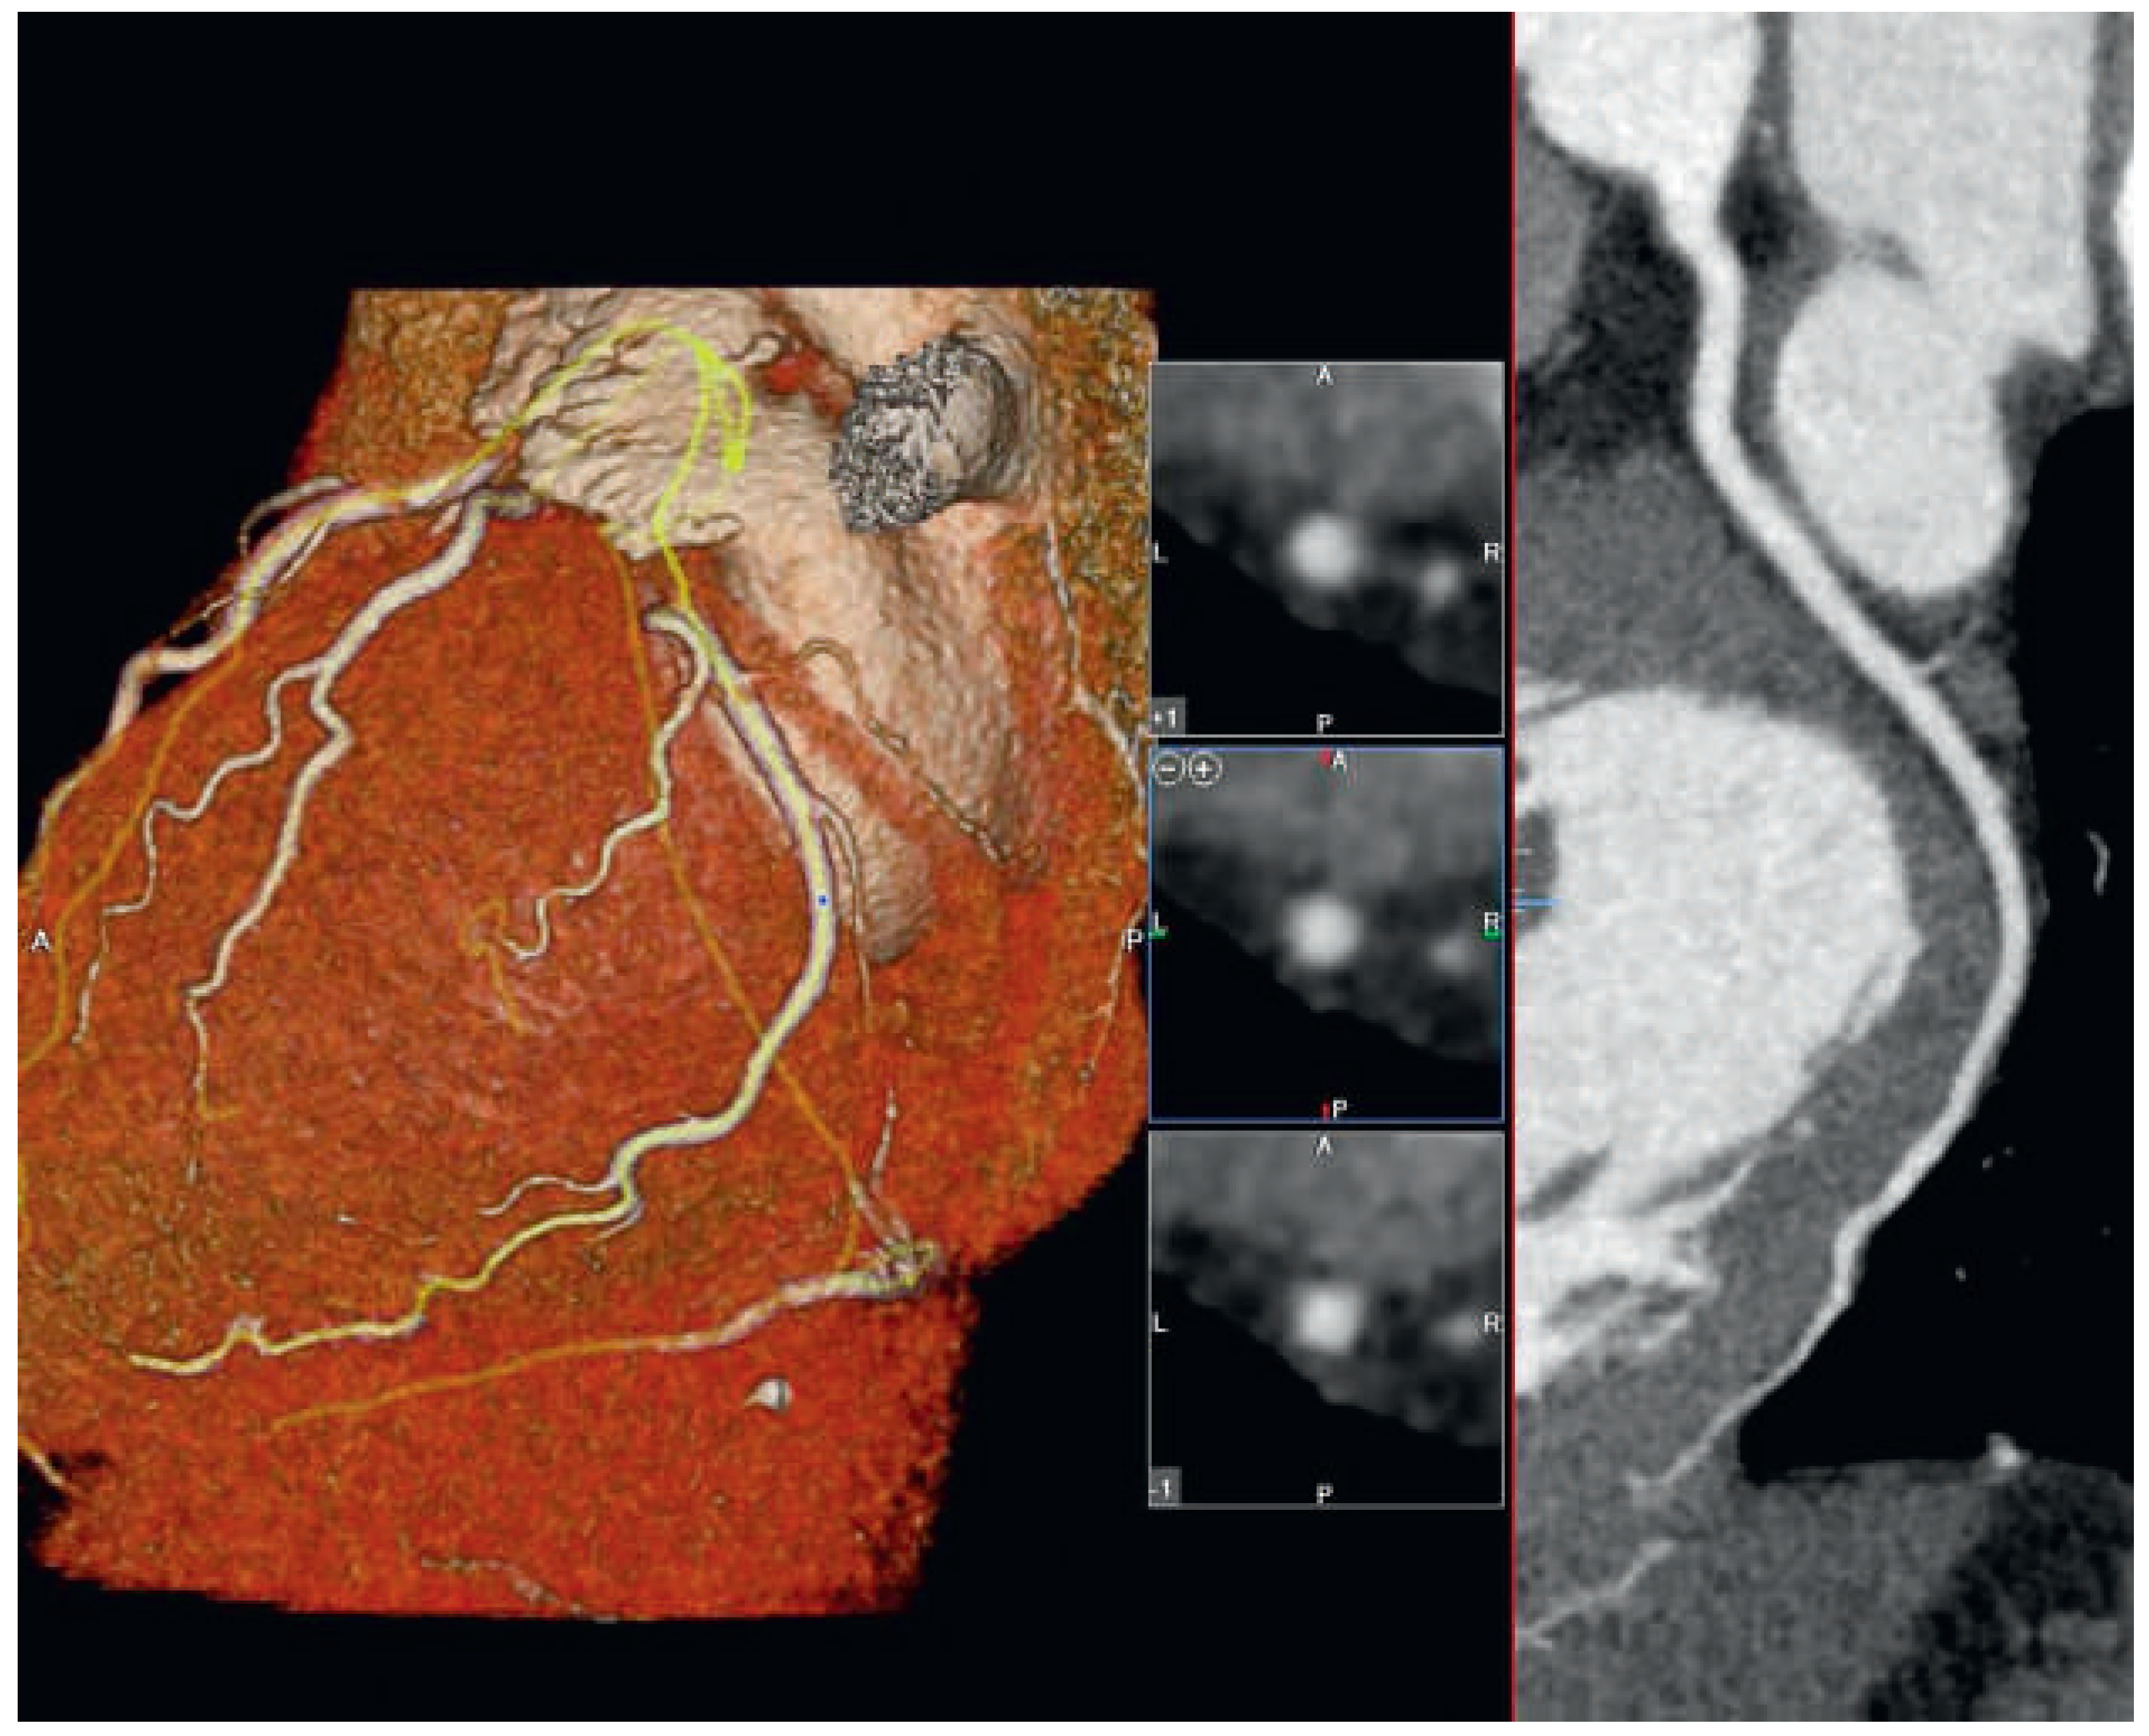

The screened population consisted of consecutive patients who presented to our out-patient clinic for cardiac evaluation (exercise electrocardiogram, stress echocardiography or invasive coronary angiography) between April 2005 and March 2007 because of suspected coronary artery disease. Ischaemic heart disease was suspected on the basis of the patient history (new-onset chest pain), a high-risk profile, or abnormal or inconclusive stress test. In all patients, CCTA was performed in addition to the standard clinical workup in order to clarify the diagnosis of possible coronary disease. Some patients were excluded because they met at least one of the following exclusion criteria: unwillingness to participate or high probability of loss in follow-up, allergy to iodine contrast agents, known cardiovascular disease and coronary artery disease on CCTA. Thus, the analytical study population consisted of 200 patients with normal CCTA. Normal CCTA was defined as well visualised coronary arteries without any calcifications, narrowing or wall abnormalities (Figure 1). Patients with soft plaques were also excluded. The study was approved by our institutions’ scientific and ethical committees, and all patients gave informed consent.

Figure 1. CCTA showing normal coronaries (left) in 3D reconstruction, normal LAD on the right.